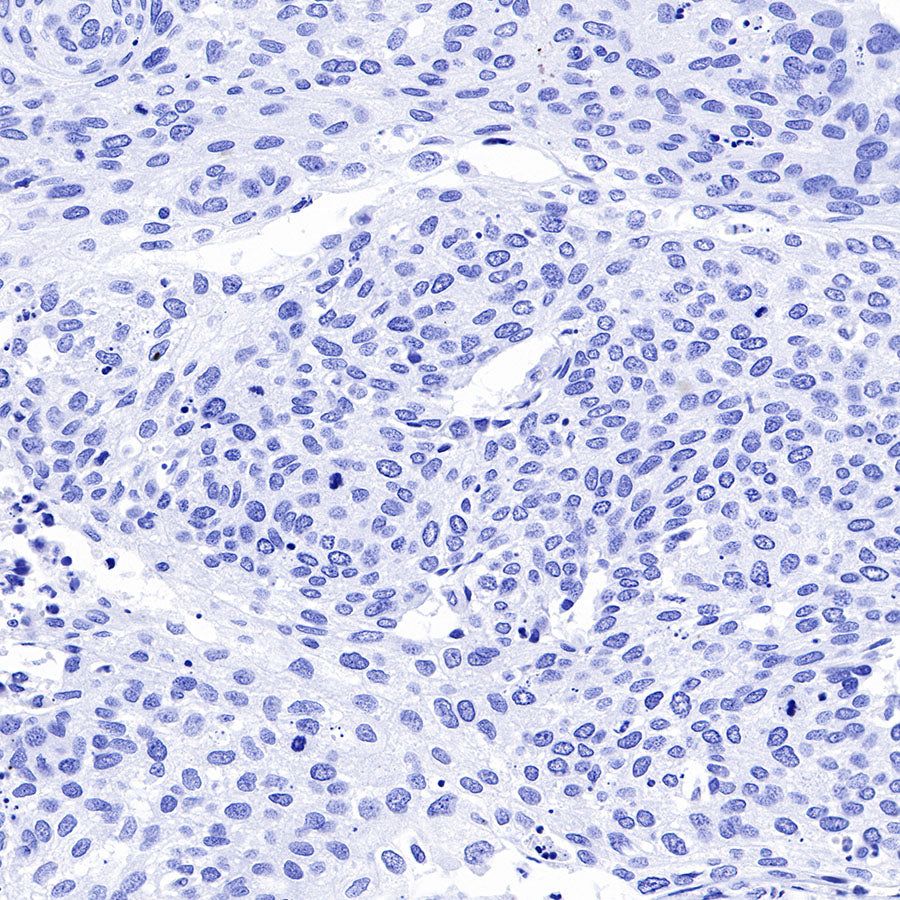

IHC shows positive staining in paraffin-embedded human colon cancer. Anti-GPA33 antibody was used at 1/2000 dilution, followed by a HRP Polymer for Mouse & Rabbit IgG (ready to use). Counterstained with hematoxylin. Heat mediated antigen retrieval with Tris/EDTA buffer pH9.0 was performed before commencing with IHC staining protocol.